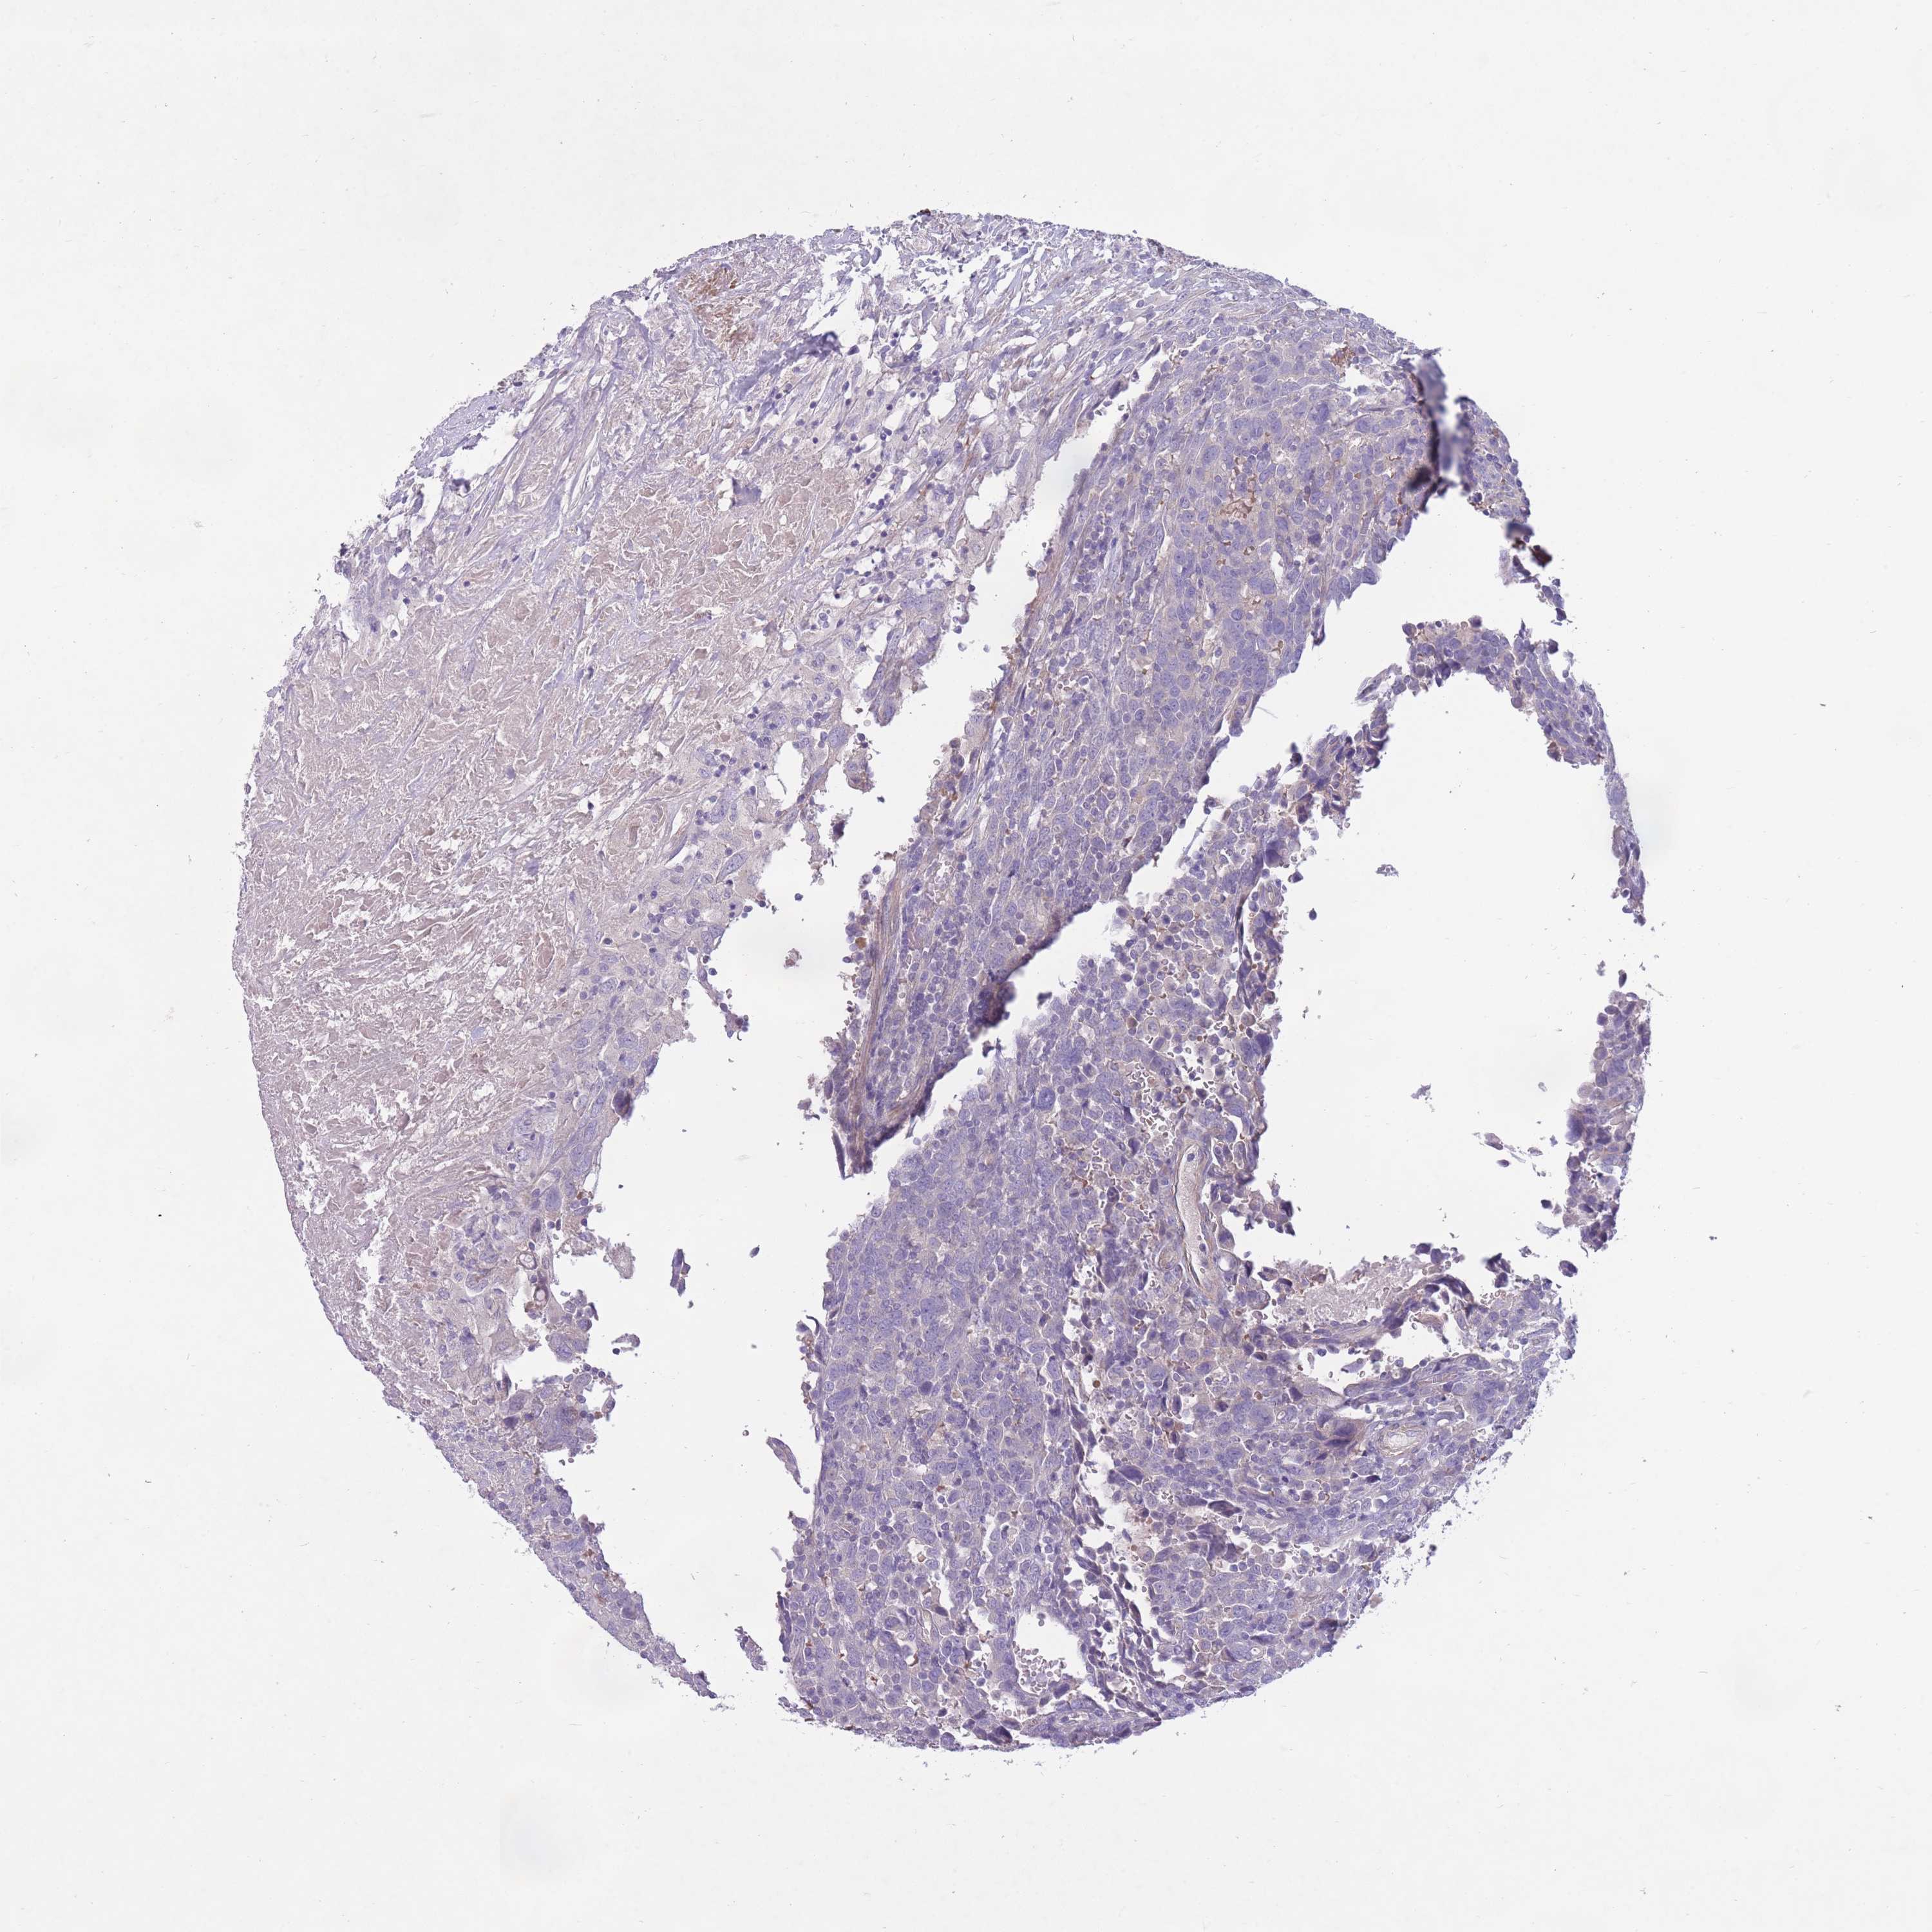

UROTHELIAL CANCER - Protein expressioni

A mouse-over function shows sample information and annotation data. Click on an image to view it in a full screen mode. Samples can be filtered based on level of antibody staining by selecting one or several of the following categories: high, medium, low and not detected. The assay and annotation is described here.

Note that samples used for immunohistochemistry by the Human Protein Atlas do not correspond to samples in the TCGA dataset.

Antibody stainingi

Antibody staining in the annotated cell types in the current human tissue is reported as not detected, low, medium, or high, based on conventional immunohistochemistry profiling in selected tissues. This score is based on the combination of the staining intensity and fraction of stained cells.

Each image is clickable and will lead to virtual microscopy that enables deeper exploration of all samples and also displays staining intensity scores, fraction scores and subcellular localization as well as patient and tissue information for each sample.

Antibody HPA050409

Antibody HPA054211

Staining

High

Medium

Low

Not detected

Intensity

Strong

Moderate

Weak

Negative

Quantity

>75%

75%-25%

<25%

None

Location

Nuclear

Cytoplasmic/membranous

Cytoplasmic/membranous,nuclear

Urothelial carcinoma, Low grade

Urothelial carcinoma, High grade

Urothelial carcinoma, NOS